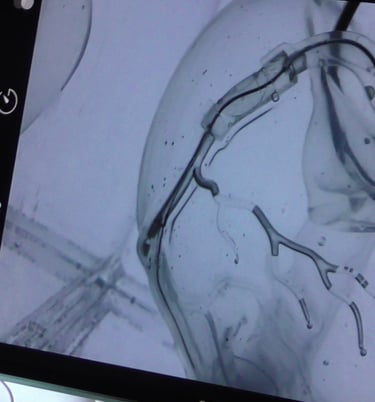

La cardiologie interventionnelle est une profession médicale passionnante. Son objectif principal est de repousser les limites de la cardiologie en utilisant des techniques avancées pour traiter les maladies cardiaques. Grâce à notre passion pour la recherche, nous sommes constamment à l’affut de nouvelles découvertes et de nouvelles technologies pour améliorer les soins aux patients.